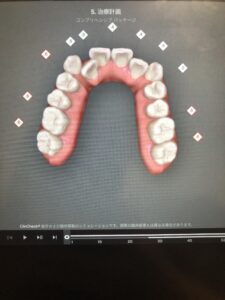

10枚目のアライナーを付ける頃にはこんな歯並びに。

正面からは変化しているように見えませんが、角度を変えてみると奥歯の辺りに隙間ができているのがわかります。